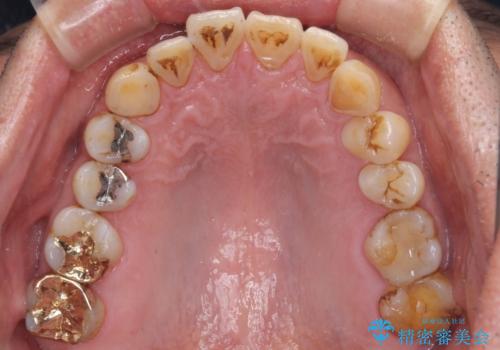

- 銀歯やインレーが外れたまま放置された奥歯の治療を希望して来院された患者様です。

咬合力が著しく強いため、欠損の多い歯はフルジルコニアクラウンへ、その他の虫歯はゴールドインレー(PGAインレー)にて修復することとしました。

来院時は全てセラミックでの治療を希望されていましたが、歯列や咬み合わせから咬合力による破損リスクが高いと判断されたため、ゴールドインレーを選択しました。